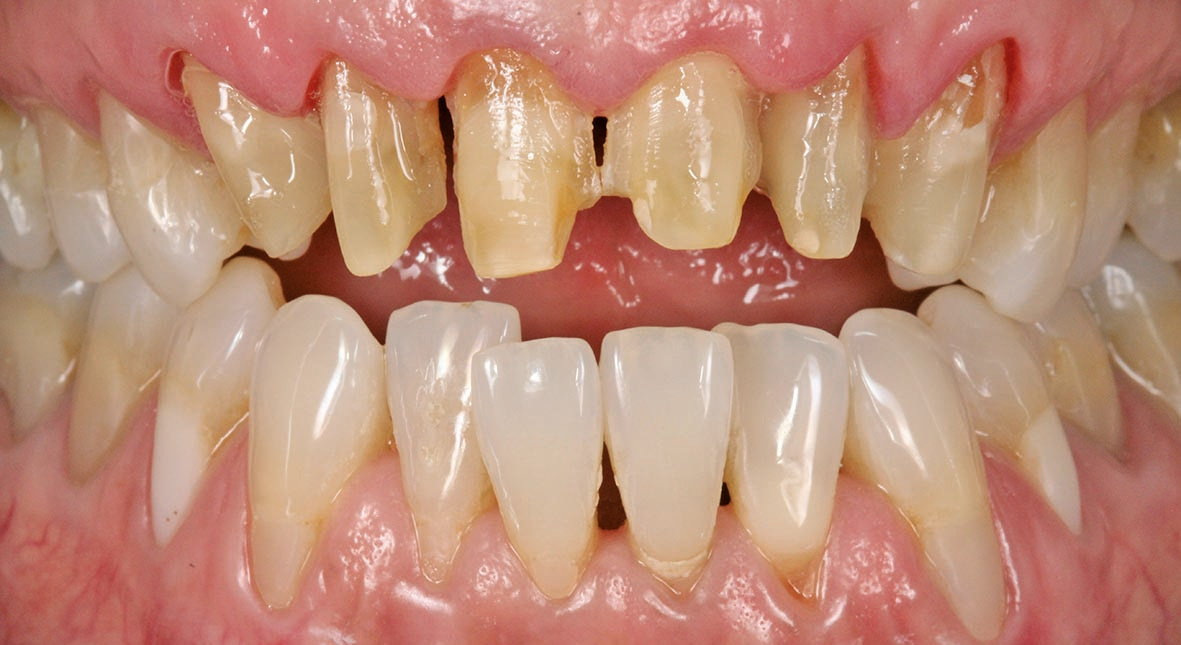

Unsere Patientin stellte sich mit einer starken Parodontitis (Abb. 1a–c) und einer schlechten Mundhygiene in der Praxis von Zahnarzt Andreas Klinkisch (Weidenberg und Bischofsgrün) vor. Am Anfang standen zunächst die Motivation zur besseren Mundhygiene, dann die konkrete Anleitung zum gründlichen Zähneputzen und schließlich die Begleitung der Maßnahmen. Nach diesem Prozess, der fast ein Jahr beanspruchte, stellte sich die 67 Jahre alte Patientin bei mir mit dem großen Wunsch vor, wieder natürliche, ästhetische und etwas hellere Frontzähne mit geschlossenen interdentalen Bereichen zu haben.

Wir sehen uns in derart gelagerten Fällen stets mit mehreren Herausforderungen konfrontiert, vor allem mit diesen: Zum einen müssen die Materialien zuverlässig und robust sein, zum anderen sollen mir die Materialien erlauben, feinste altersspezifische und individuelle Merkmale zu berücksichtigen und „nachzubauen“. Bei dieser Patientin waren die Zähne leicht fluoreszierend, das inzisale Drittel transparent und in der Schneidekante leicht opaleszent. Das Dentin und der Zahnhalsbereich hingegen wirkten stark chromatisch. Auch wollten wir, dass sich das Zahnfleisch bestmöglich an das Material adaptiert. Auch das würde helfen, die schwarzen Dreiecke im Frontbereich zu schließen.